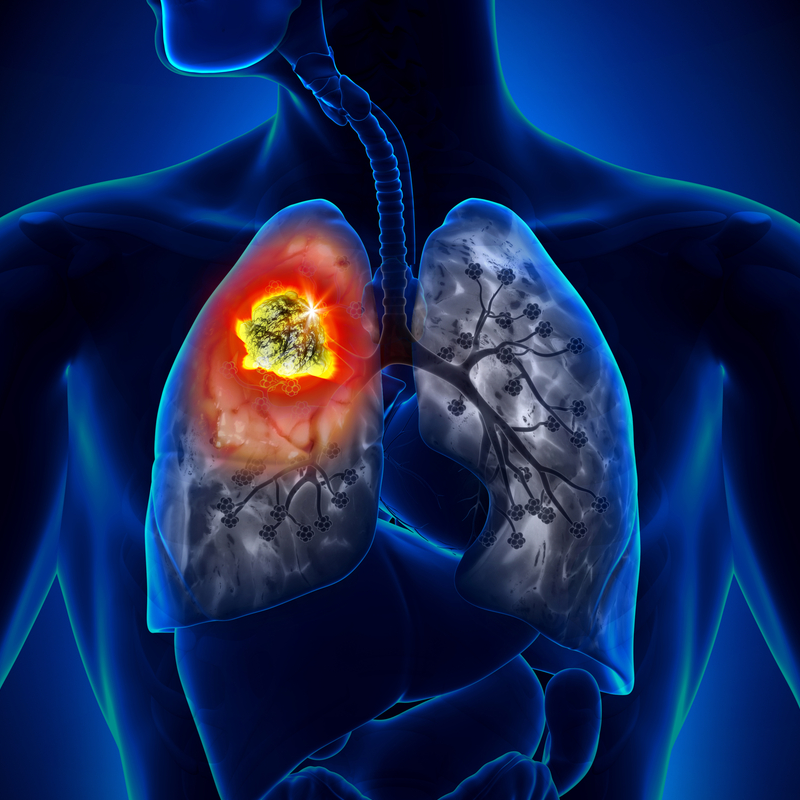

كتل غير طبيعية

- العقدة اللمفاوية

- العقدة الرئوية

- عقدة الغدة الدرقية

- عقدة الصدر

العقدة الرئوية